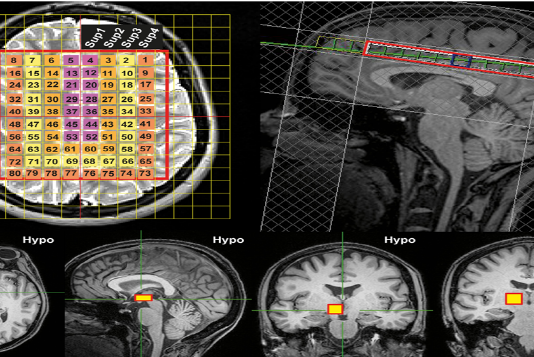

인간의 뇌 온도는 체온보다 약 2도가 높은 평균 38.5도로 나타났다. 특히 여성의 경우 하루 중 낮 동안에는 뇌 깊은 곳의 온도가 40도를 넘는 것으로 나타났다.기존 인간의 뇌 온도 측정은 뇌 손상을 입은 중환자의 뇌에 탐침을 통해 직접 측정했다. 하지만 이번에는 뇌 속을 직접 접촉하지 않는 비침습적 방법으로 뇌 온도를...